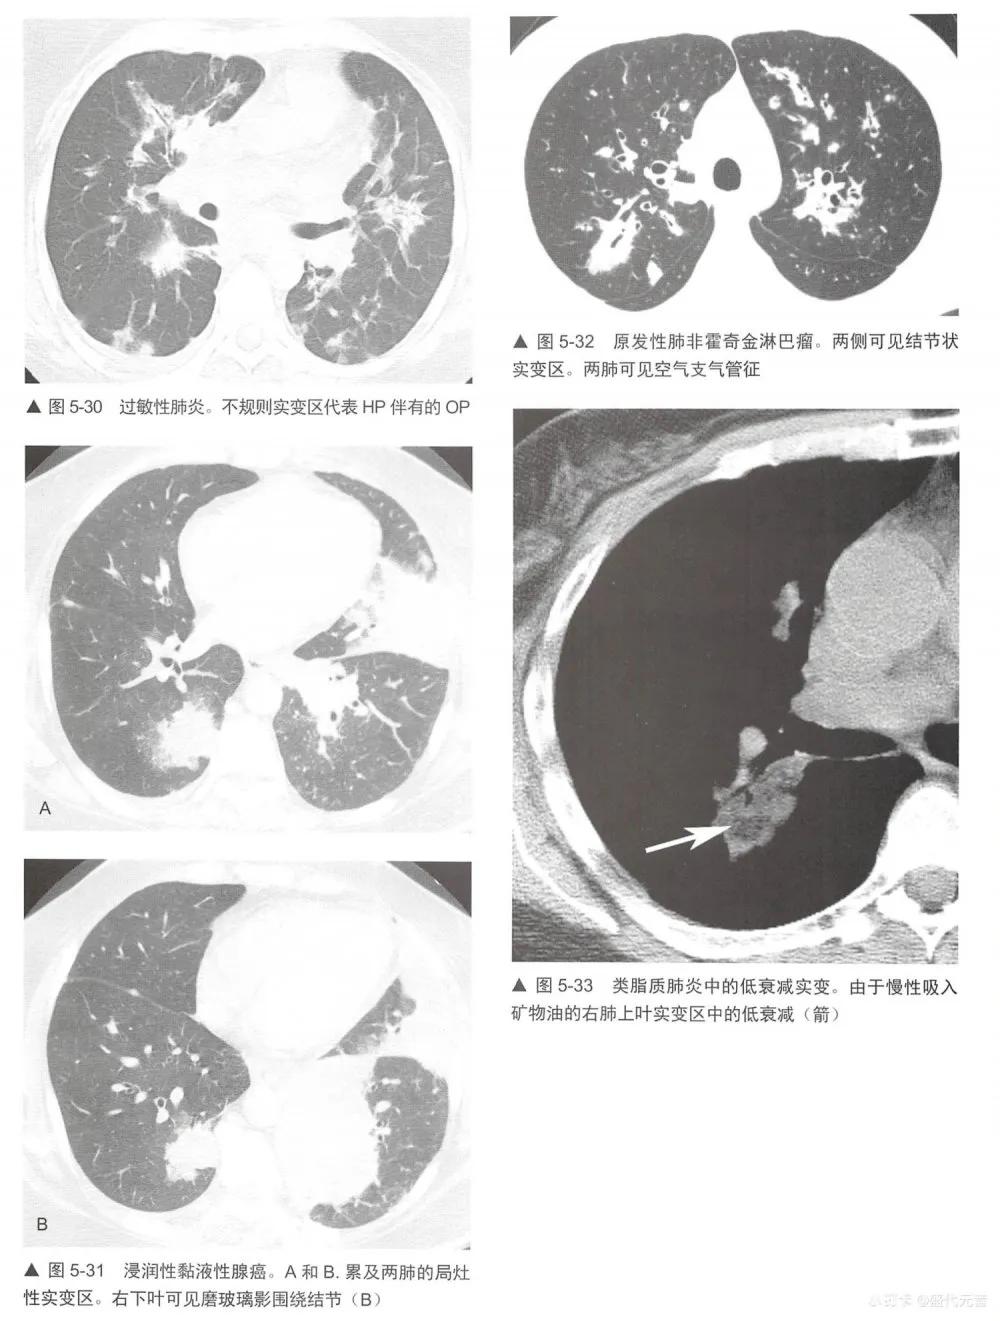

实变的鉴别诊断与磨玻璃影(表5-1)有相当大的重叠,事实上,许多表5-1列出的疾病都显示为这两种表现的混合(表5-5)。实变的鉴别诊断包括不同原因的肺炎:最典型的是细菌性(图5-28),但也包括分枝杆菌、真菌性肺炎(图5-29)、支原体、耶氏孢子菌和病毒性肺炎; 0P (图5-24和图5-25);嗜酸性肺炎(图5-26,图5-27),如NSIP和DIP的间质性肺炎;HP (图5-30);放射性肺炎、浸润性黏液腺癌(图5-16和图5-31); LIP;淋巴瘤(图5-32)和淋巴增生性疾病;肺泡蛋白沉着症;结节病;药物反应,肺水肿和肺出血;AIP, DAD和ARDS。与吸入动、植物油脂或矿物油有关的外源性类脂性肺炎,可导致磨玻璃影或实变,此时因含有脂肪是低衰减的(图5-33)。